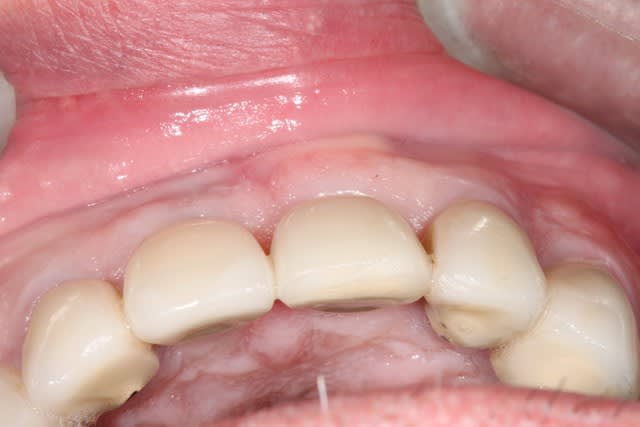

1/ photo pré op

photo de controle vue vestibulaire et occlusale 8 mois post chir

puis à 2 ans post op

on constate que contrairement à la 11 surlaquelle il y a un affaissement de l'os vestibulaire

sur la 21 le volume est préservé

Si je peux me permettre, la 11 semble plus naturelle, car le zénith gingival est plus ovoide. La 21 possède certe plus de volume de tissu en vestibulaire, mais le collet gingivale est trop coronaire, effet de dent trapue.

L'ensemble est par contre sympa.